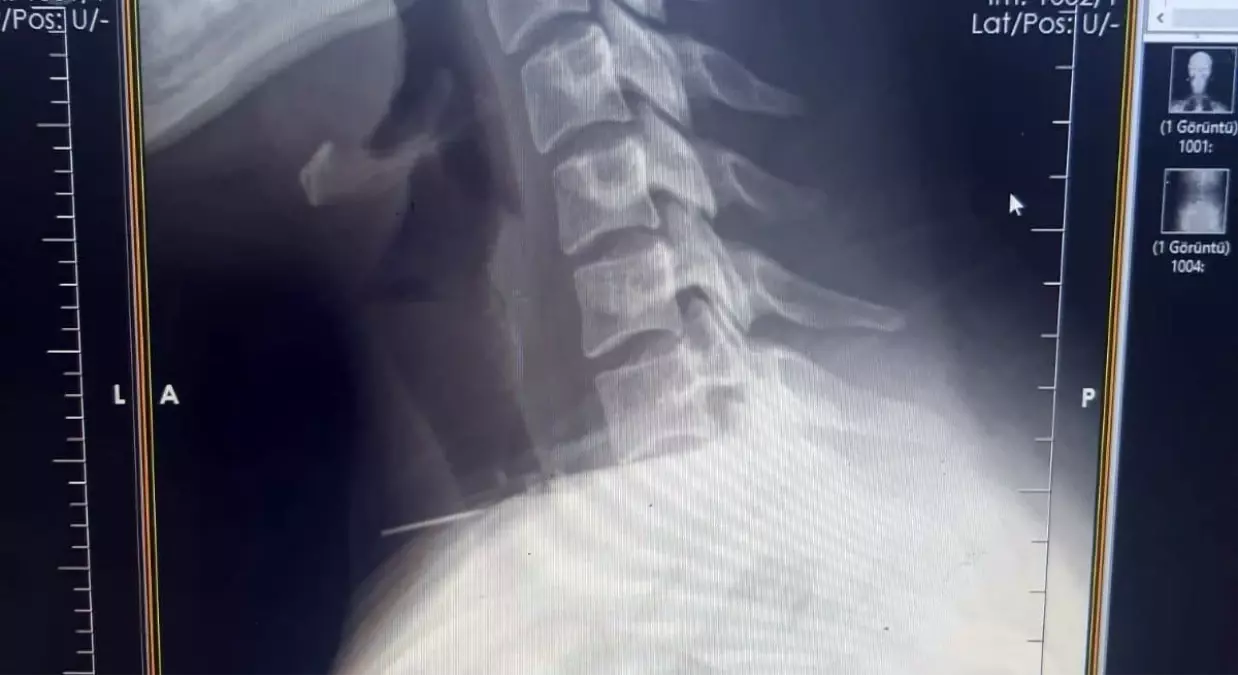

Radyolojik incelemeler ve klinik değerlendirmeler sonucunda, 3 santimetrelik iğnenin boğaz bölgesinin derinliklerine doğru ilerlediği tespit edildi.

İğne, yaklaşık 1 saat süren ameliyatla çıkarıldı. Ameliyat sonrası süreci sorunsuz atlatan hasta taburcu edildi.